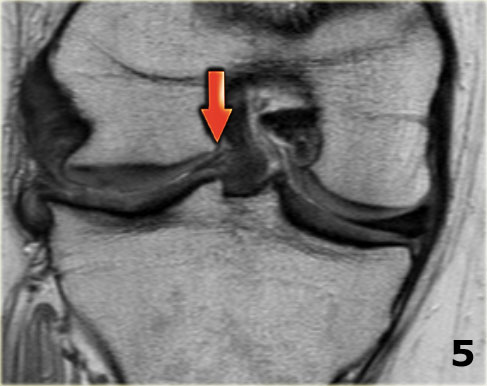

Bên trái là các hình ảnh PD sagittal của một trường hợp sụn chêm lật.

Toàn bộ sừng sau bị lật ra phía trước, tạo ra dấu hiệu sụn chêm rỗng (empty meniscus sign) (mũi tên).